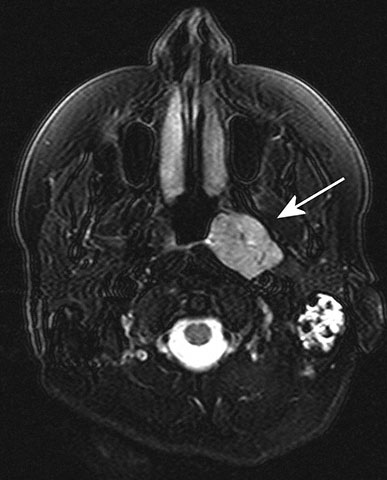

44. Question

A 75-year-old man is brought to the physician because of a 2-month history of increasingly severe discomfort in his left ear. Audiometry shows severe conductive deafness of the left ear. Auriscopy shows a bulging tympanic membrane of the left ear. Indirect laryngoscopy shows a mass in the nasopharynx on the left. A T2-weighted MRI of the brain is shown; the arrow indicates a mass. This mass has most likely caused occlusion of which of the following structures?